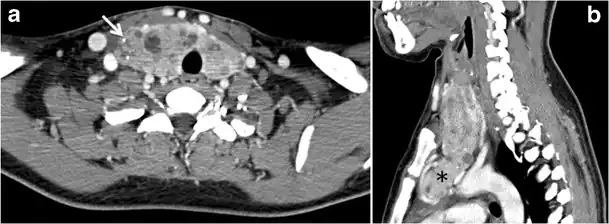

Fig. 13. A 27-year-old female patient known to have goiter. a, b Axial and sagittal enhanced CT scan images of the neck demonstrate a heterogeneously enhancing, enlarged thyroid gland with scattered calcifications (white arrow), cystic changes, and substantial retro-sternal extension (black asterisks). No lymphadenopathy or substantial airway narrowing.[1] -